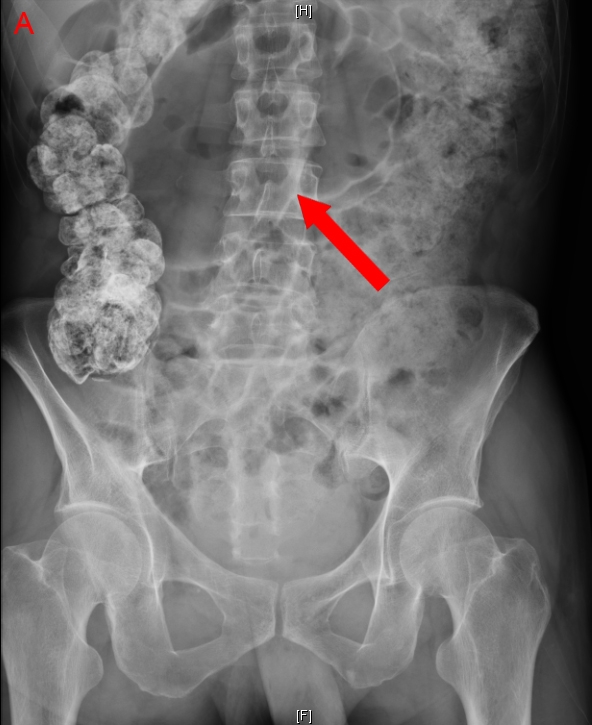

Plain abdominal radiographs in patients with toxic megacolon classically reveal thick haustral markings that do not extend across the entire lumen.

On KUB (kidney, ureter, bladder) radiographs, a classic "coffee bean sign" may be seen, indicating a sigmoid volvulus.

In the presence of a volvulus, the distal duodenum and proximal jejunum course downward in the mid abdomen. On contrast radiography, this may be seen as a “corkscrew” appearance. The lumen also becomes narrowed and may have a “beaked” appearance at the level of obstruction.